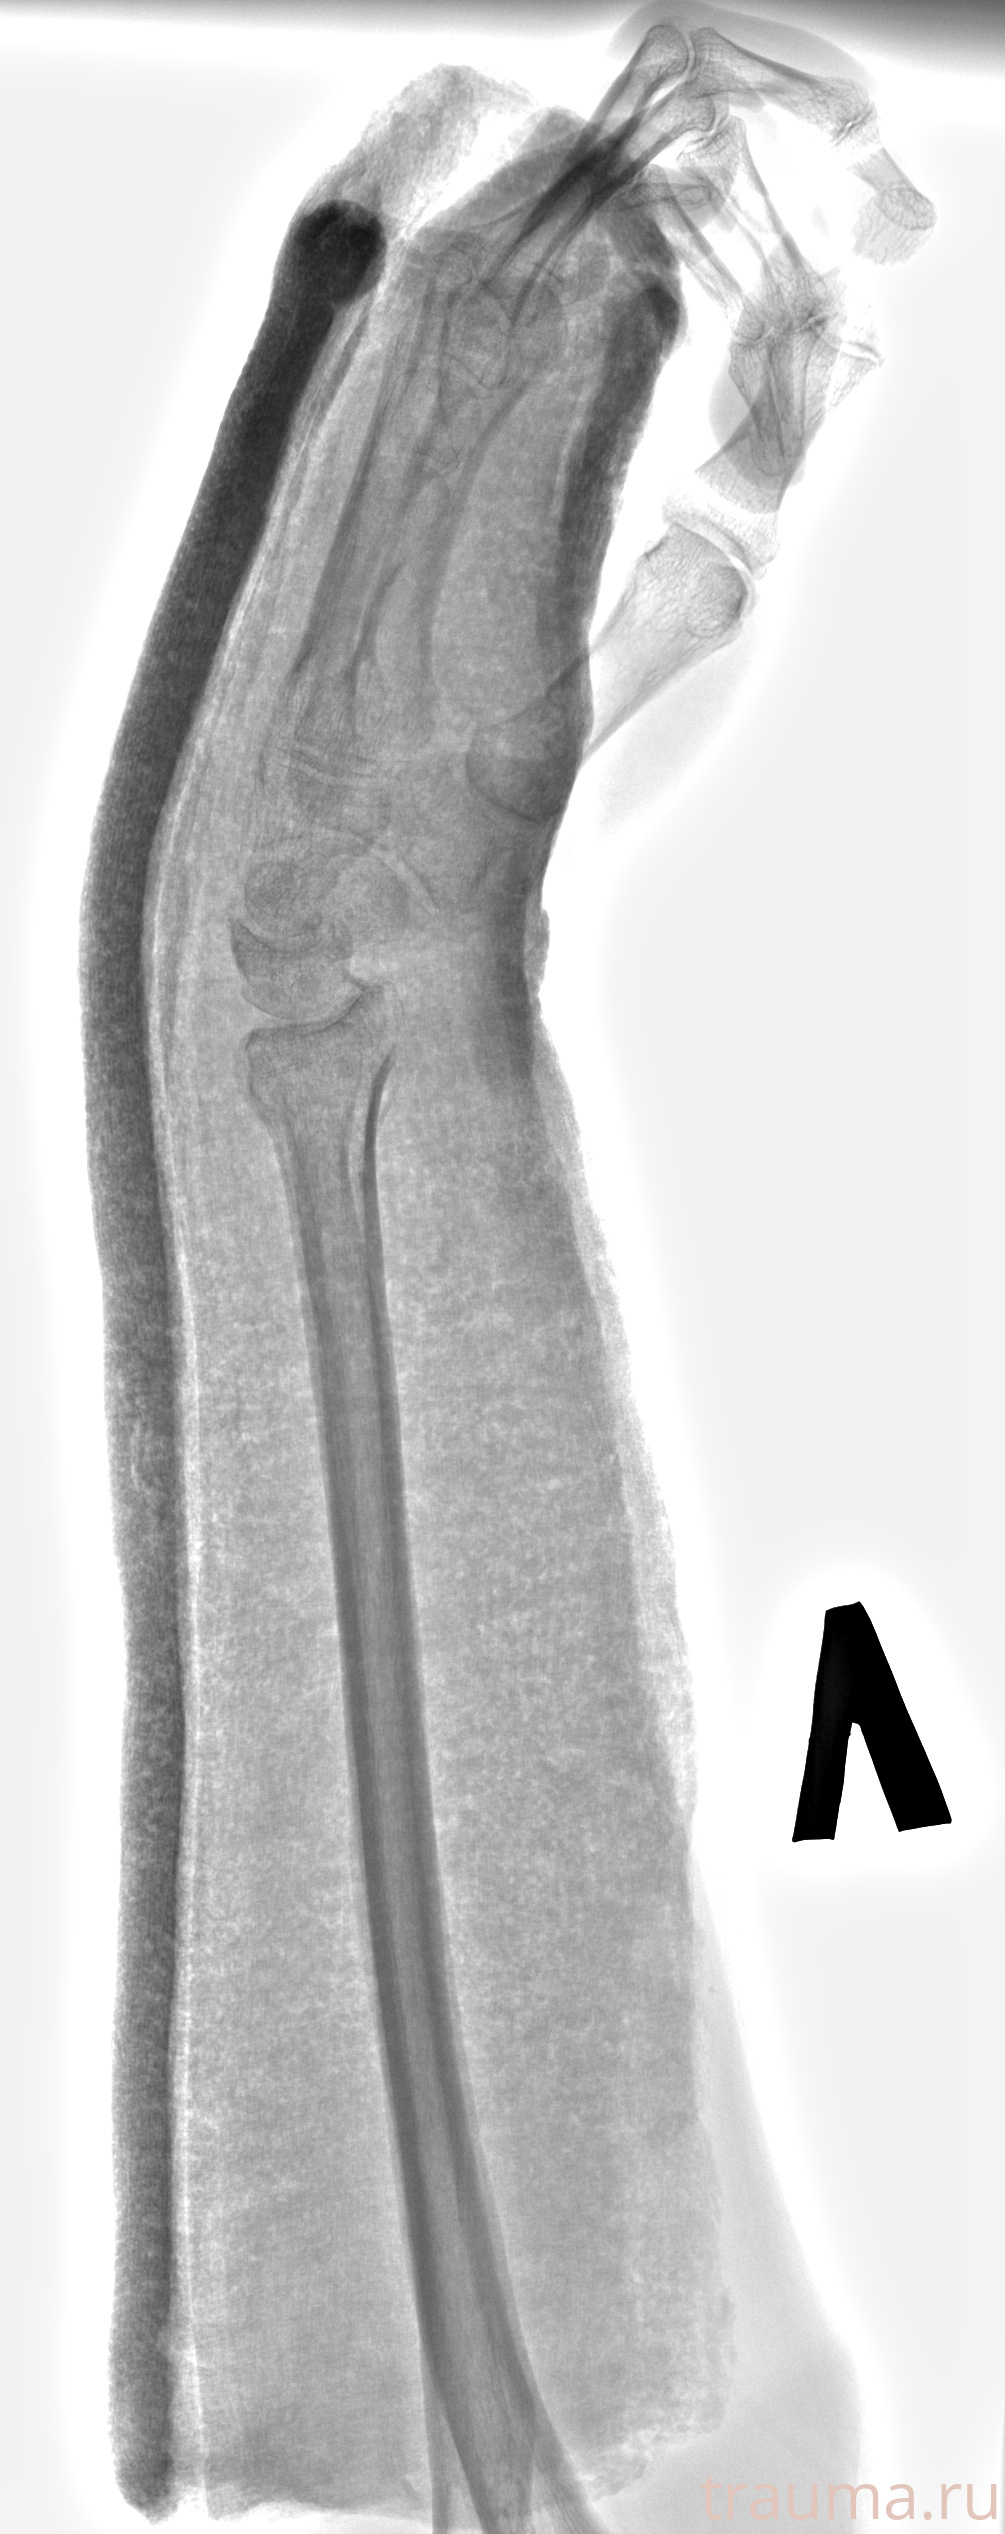

Рентгенограммы

Рентген на дому: по вашему адресу приезжает врач-рентгенолог, травматолог-ортопед с мобильным рентгеновским аппаратом, проводит диагностику травмы или заболевания, делает необходимые рентгенограммы, дает рекомендации по дальнейшему лечению. Получить качественные снимки в домашних условиях возможно благодаря уникальной методике, разработанной МосРентген Центром для института  Склифосовского